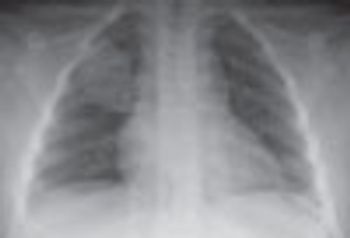

A 5-year-old boy with a history of allergies and asthma presents with fever (temperature of 40°C [104°F]), headache, cough, vomiting, and diffuse pain in and around the chest area on the right side. The patient has never traveled and has no sick contacts. A chest radiograph is obtained (A).